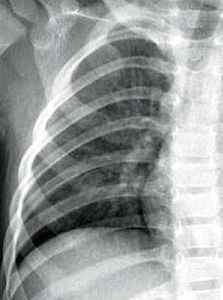

3 胸部X線檢查:肺葉或肺段分布的均勻緻密的大片狀實變陰影可確診。

胸部X線檢查都會顯示肺浸潤,但在最初數小時可表現不明顯或難以發現。支氣管肺炎是最常見的X線表現,但實變局限於一葉的大葉性肺炎伴典型支氣管充氣征是肺炎球菌感染的特殊表現。